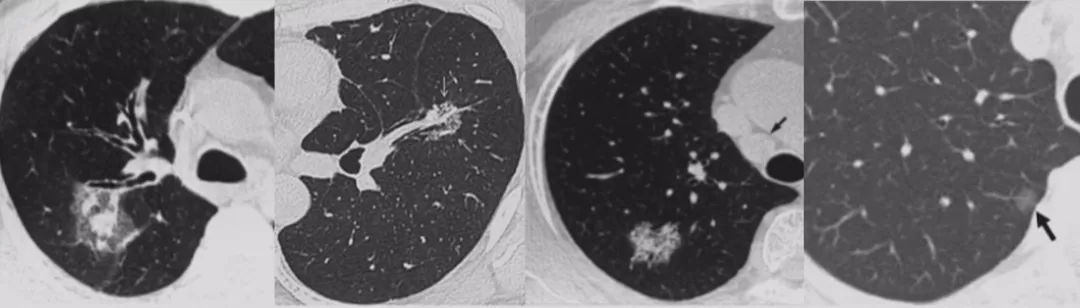

CT随访

1)病灶大小无变化、实性成分增多

这个结节大小没有太大变化,实性成分增多,这不是一个好征象,可以考虑手术。

2)病灶缩小、出现实性成分

容易被大家忽略的是结节的大小变小,但实性成分增多,值得大家重视。不要认为结节变小了就一定是良性。